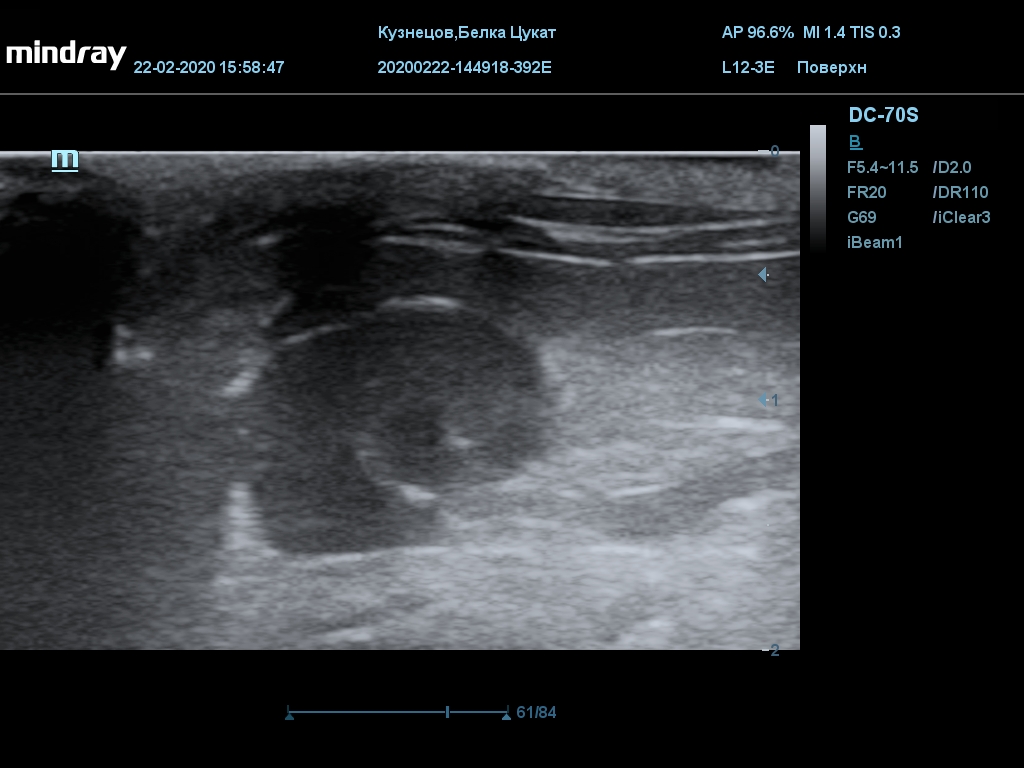

УЗИ

(почки, мочевой пузырь и, предположительно, простата)

Обращаю внимание, что делала УЗИ и писала заключение узист, которая специализируется на кошках и собаках, поэтому она сделала узи и описала, как смогла, но тонкостей грызунячьей анатомии она не знает.

Приложил только фото, есть ещё пара видео, но не знаю, как тут выложить, и надо ли.

Каудальнее мочевого пузыря визуализируется округлая структура размером 11,1 х 8,3 мм с ровными контурами гипоэхогенная однородная, с признаками васкуляризации.

Заключение: УЗпризнаки уролитиаза, объёмная структура каудальнее мочевого пузыря. Признаки расширения левой лоханки.

УЗИ

(почки, мочевой пузырь и, предположительно, простата)

Обращаю внимание, что делала УЗИ и писала заключение узист, которая специализируется на кошках и собаках, поэтому она сделала узи и описала, как смогла, но тонкостей грызунячьей анатомии она не знает.

Каудальнее мочевого пузыря визуализируется округлая структура размером 11,1 х 8,3 мм с ровными контурами гипоэхогенная однородная, с признаками васкуляризации.

Заключение: УЗпризнаки уролитиаза, объёмная структура каудальнее мочевого пузыря. Признаки расширения левой лоханки.